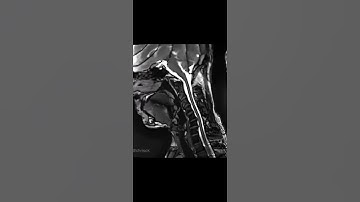

C-spine - 30% time reduced MRI scan. iQMR Image Enhancement and Sharpening